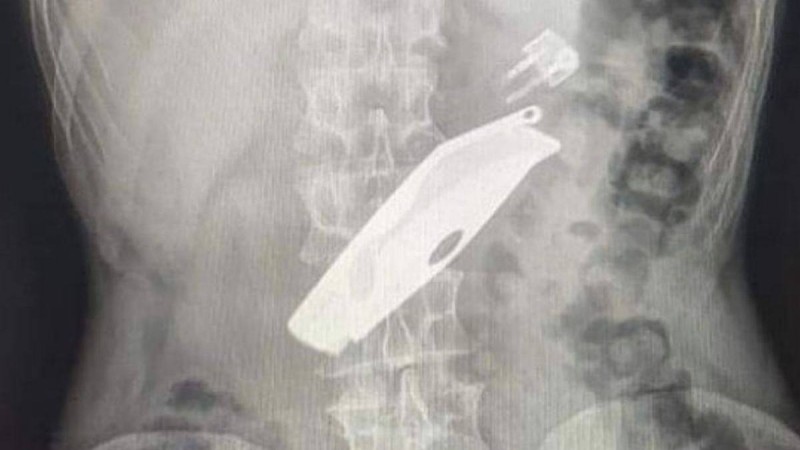

"Отбасылық күйзеліске түскендіктен істедім": СҚО-да ер азамат бәкі мен шақпақ жұтып, өліп кете жаздады - Қазақстан жаңалықтары Солтүстік Қазақстан облысында дәргерлер ер азаматтың асқазанынан бәкі пен шақпақты... 28 сәуір 2020 • Шоу-бизнес